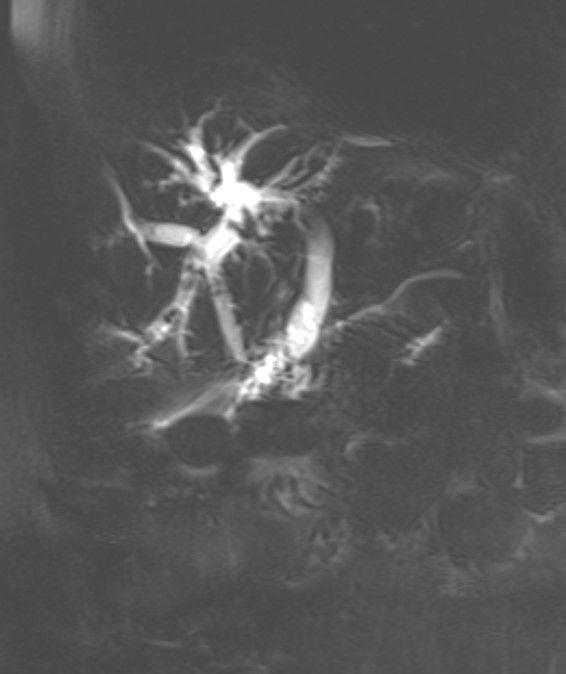

吴军了解到患者及家属的诉求后,对患者进行了更全面的术前评估,并组织了多学科会诊,确定了最终的手术治疗方案。由吴军带领的普外科专家团队为患者进行了直视下腹腔粘连松解+胆总管切开取石+胆道镜下胆道探查、取石冲洗+肝IVb段部分切除+肝门胆管盆状成形+胆管空肠内引流+十二指肠憩室穿孔修补+T管引流术。术中可见腹腔粘连严重,肝脏面广泛膜性粘连,寻找目标胆管极为困难,经肝表面触诊明确“结石感”,术中予切除IVb段部分肝组织,找到右肝管汇入肝总管明显狭窄处,并解除这处最主要的手术难点,术中阻力重重,手术难度极高!历经艰难的多个小时,克服手术中的重重困难,手术非常成功!